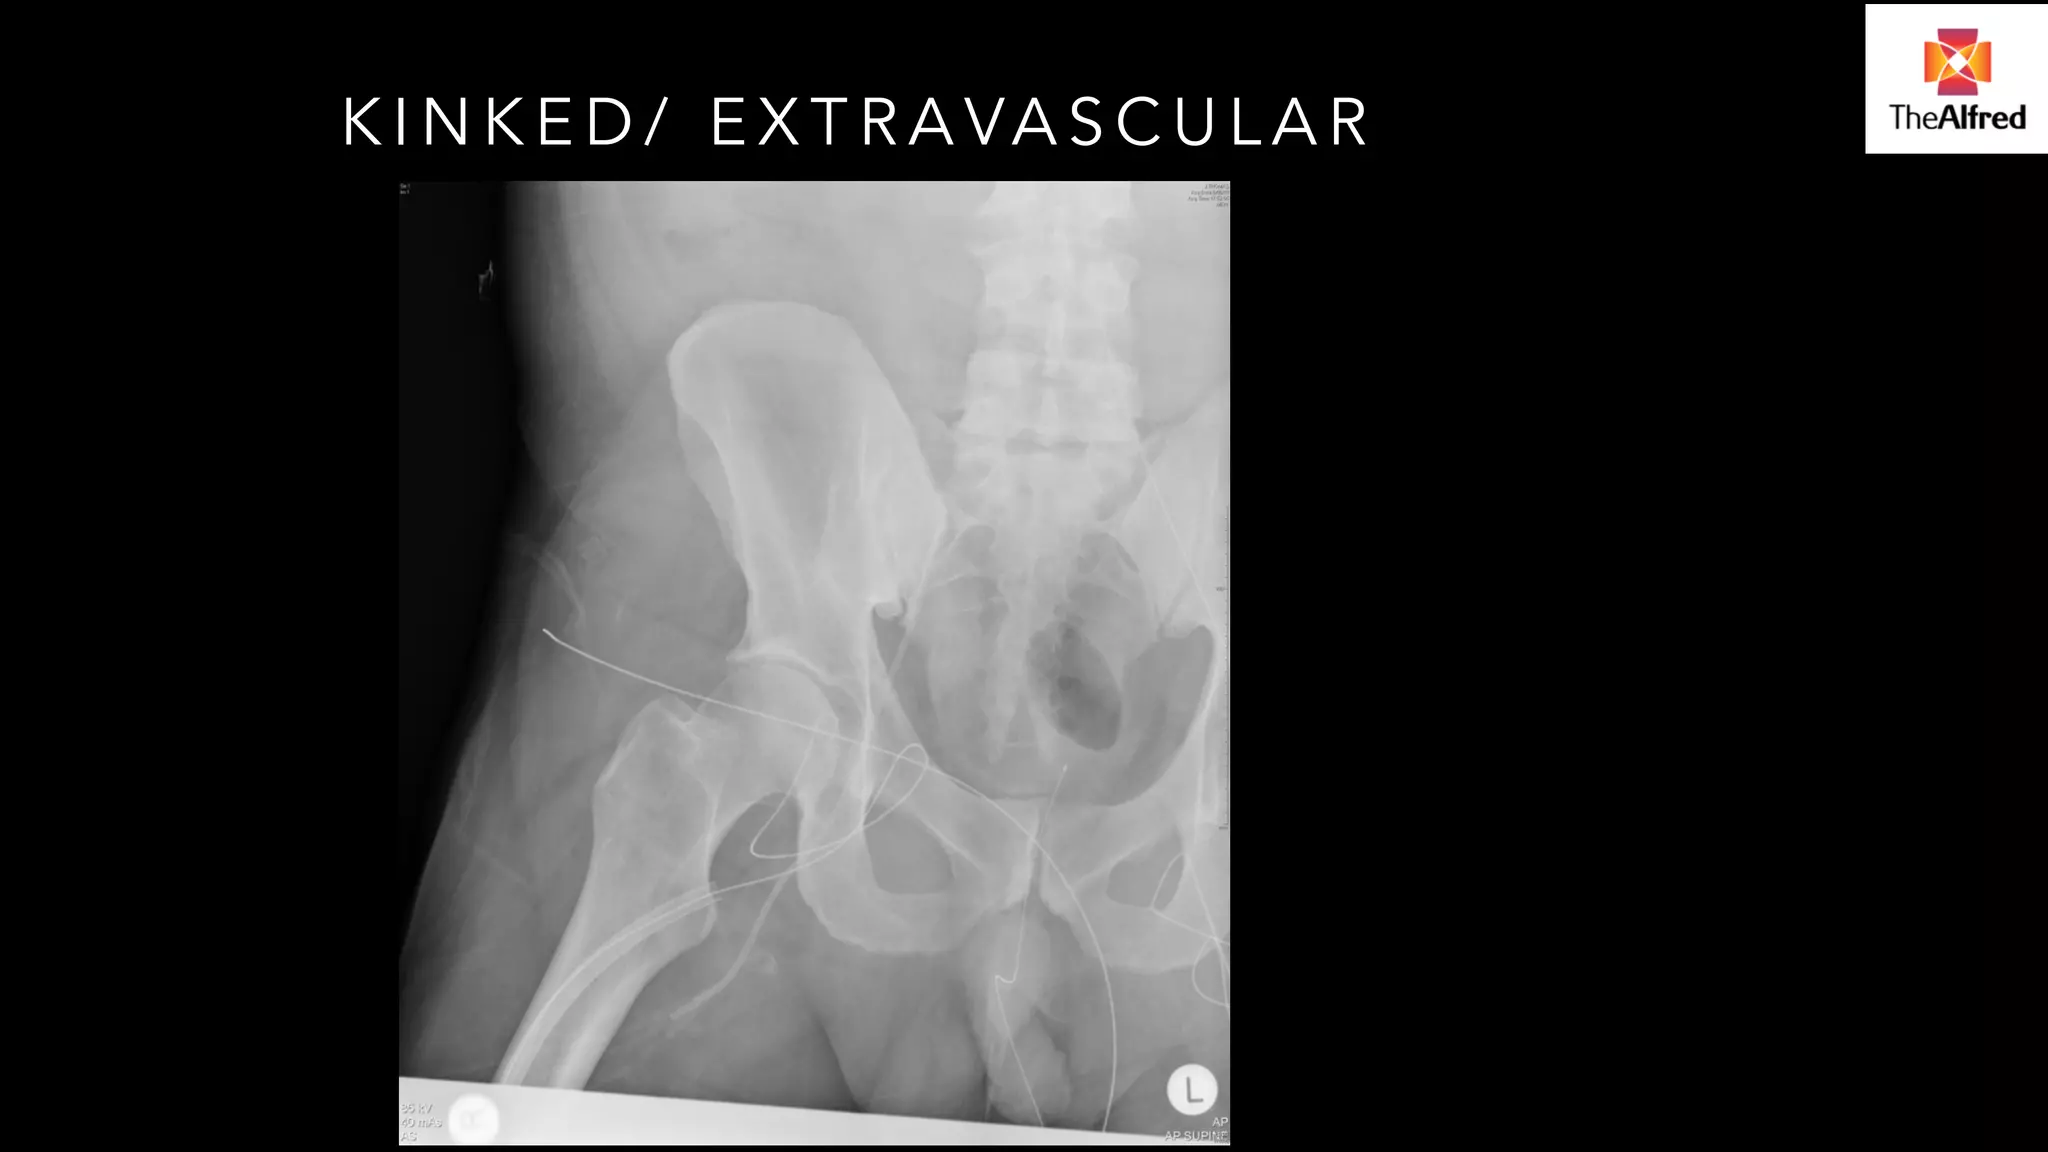

KINKED/ EXTRAVASCULAR

DEEP PELVIC OBSTRUCTION KIT

Stiff guidewire (e.g. Amplatz)

Long exchange catheter to get around

tortuosity in the pelvic vessels

DEEP PELVIC OBSTRUCTIONKIT Stiff guidewire (e.g. Amplatz) Long exchange catheter to get around tortuosity in the pelvic vessels